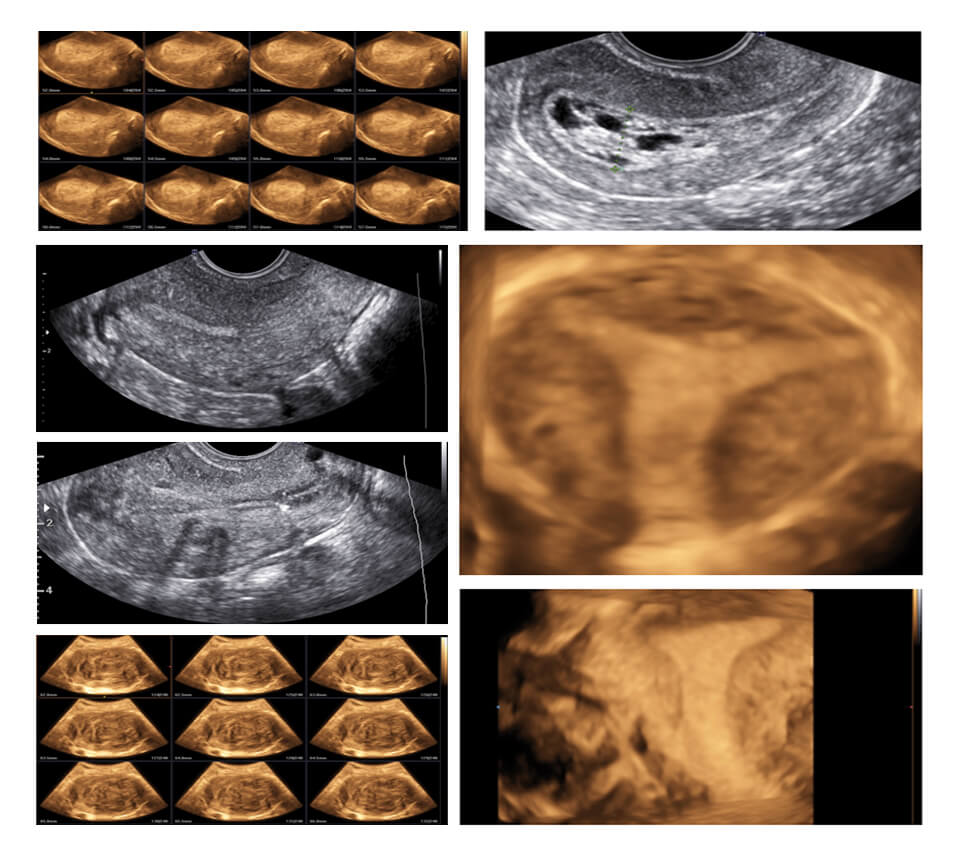

MYOENDOMETRIAL PATHOLOGIES

• BASICS OF TAS n TVS

• CLINICAL / DIAGNOSTIC AND PATHOLOGICAL CORRELATION OF MYOMETRIAL AND ENDOMETRIAL PATHOLOGIES

• LESIONS AND THEIR REFERNCE TO INFERTILITY

• TIPS AND TRICKS FOR DIAGNOSING ON ULTRASOUND

Session 1 COLOR DOPPLER KNOBS AND SETTINGS

Session 2 COLOR DOPPLER ENDOMETRIUM (NORMAL AND ABNORMAL)

Session 3 COLOR DOPPLER MYOMETRIUM (NORMAL AND ABNORMAL)

CDC : INFERTILITY

BASELINE SCAN

ENDOMETRIAL FLOW OVARIAN STROMAL FLOW

FOLLICLE MONITORING

ENDOMETRIAL ZONAL VASCULARITY UTERINE ARTERY DOPPLER PERI-FOLLICULAR VASCULARISATION FOLLICLE PSV

LUTEAL PHASE

CORPUS LUTEAL FLOW

COLOR DOPPLER CLUB

CDC : GYNECOLOGY

ENDOMETRIUM

FLOW IN DIFFERENT PHASES POLYP/HYPERPLASIA/

MALIGNANCY/ADHESION

MYOMETRIUM

FIBROIDS ADENOMYOSIS